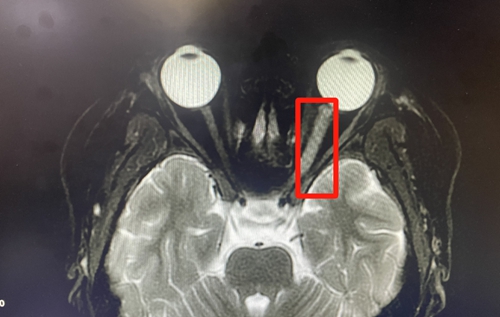

△照片來源于神經(jīng)內(nèi)科。秋秋顱內(nèi)有異常信號,左眼視神經(jīng)相比右眼明顯腫脹

神經(jīng)內(nèi)科接診醫(yī)生完善了頭顱磁共振檢查,提示秋秋顱內(nèi)有異常信號,高度懷疑中樞神經(jīng)系統(tǒng)炎性脫髓鞘疾病。

收入病房后,經(jīng)過進一步對癥化驗、檢查,確診孩子患有中樞神經(jīng)系統(tǒng)炎性脫髓鞘疾病,而引起脫髓鞘的原因是“MOG抗體相關疾病”。